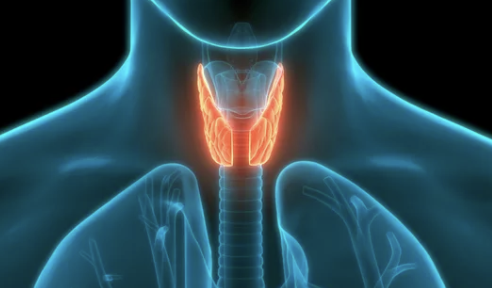

4-1. 갑상선 기능 항진증

- 갑상선 호르몬 과다 분비로 인해 신진대사가 활발해지며, 손이 떨리는 증상이 나타납니다.

- 동반 증상:

- 체중 감소, 심박수 증가, 과도한 땀 분비.